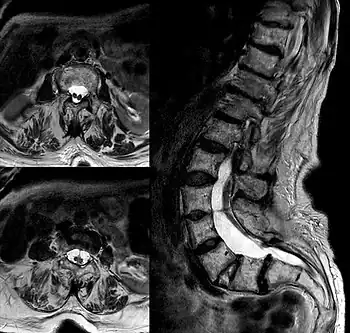

Diastematomelia in MRI of lumbar spine.

Diastematomyelia (occasionally diastomyelia) is a congenital disorder in which a part of the spinal cord is split, usually at the level of the upper lumbar vertebra in the longitudinal (sagittal) direction. Females are affected much more commonly than males. This condition occurs in the presence of an osseous, cartilaginous or fibrous septum in the central portion of the spinal canal which then produces a complete or incomplete sagittal division of the spinal cord into two hemicords. When the split does not reunite distally to the spur, the condition is referred to as diplomyelia, which is true duplication of the spinal cord.[1]

Adult presentation in diastematomyelia is unusual. With modern imaging techniques, various types of spinal dysraphism are being diagnosed in adults with increasing frequency. The commonest location of the lesion is at first to third lumbar vertebrae. Lumbosacral adult diastematomyelia is even rarer. Bony malformations and dysplasias are generally recognized on plain x-rays. MRI scanning is often the first choice of screening and diagnosis. MRI generally give adequate analysis of the spinal cord deformities although it has some limitations in giving detailed bone anatomy. Combined myelographic and post-myelographic CT scan is the most effective diagnostic tool in demonstrating the detailed bone, intradural and extradural pathological anatomy of the affected and adjacent spinal canal levels and of the bony spur.